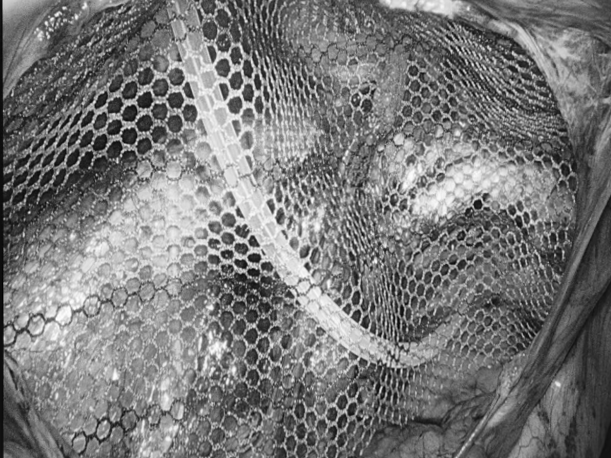

8月27日,贵州航天医院第75次晨读会由我院柔性引进的知名肛肠外科专家高大勇教授作学术交流,他以“肛肠科常见病浅谈”为题,系统讲解了痔疮、肛裂、肛周脓肿等常见肛肠疾病的症状表现、潜在风险及相应治疗方式,为医院带来了前沿医疗理念与技术,有效提升了医务人员对肛肠疾病的早期识别与诊疗水平,也为学科建设、临床诊疗能力的长效提升奠定了坚实基础。 贵州航天医院 普外科专家简介 高大勇 普外科(肛肠外科)学科带头人、名誉主任,主任医师、教授 临床擅长:对中西医结合诊治肛肠学科各种常见病、多发病及疑难杂症等具有丰富的临床经验。 原遵义市第一人民医院(遵义医科大学第三附属医院)、遵义市中医院肛肠科主任。中华中医药学会肛肠分会常委,全国中医肛肠学科名专家,中国健康促进与教育协会肛肠分会常委,中国康复医学会肛肠疾病康复专业委员会常委,中国民间中医医药研究开发协会肛肠分会副秘书长,中国医师协会中西医结合肛肠医师专业委员会常委,国家二级心理咨询师,贵州省第一批中医名医工作指导老师,遵义市名中医,遵义市肛肠学会会长,遵义市肛肠质控中心名誉主任,遵义市中西医结合学会名誉会长,遵义市健康科普专家,原贵州省中西医结合学会肛肠分会副主任委员、贵州省中医肛肠质控中心副主任、遵义市医学会医疗鉴定委员会专家、遵义市卫生系列高评委。发表论文30余篇,主编和参编医学著作5本,主持省级科研课题2项、市级科研课题2项、院级科研课题1项。 梁   跃 中共党员,普外科党支部书记、主任,主任医师 临床擅长:对普外科各类肿瘤手术具有丰富的临床经验。 毕业于遵义医学院,遵义市医学会小儿外科学分会常务委员,遵义市肛肠协会理事,遵义市医学会核医学分会(第二届)委员会委员;荣获第三期“黔医人才计划”优秀学员称号;主持市级课题1项,完成省级课题1项,在国内各类刊物上发表论文10余篇。 钱科洪 民盟盟员,普外科副主任医师 临床擅长:从事普外科临床工作30余年,对各类普外科疾病的诊治、乳腺、甲状腺、胃十二指肠、结直肠等疾病及疑难杂症具有丰富的临床经验。 毕业于遵义医学院临床医疗系,2009年前往中山大学附属第一医院微创外科进修学习,在国内各专业期刊发表论文数篇。 贵州航天医院 普外科简介 基本情况 贵州航天医院普外科成立于1968年,前身属于航天部O61基地3417医院外一科,1998年3417医院、3427医院合并后更名为普外科,下设胃肠外科、肛肠外科2个亚专业科室,拥有在全市较为先进的专科设备和技术,是中国疝病专科联盟单位,贵州医科大学附属医院胃肠外科专科联盟单位。开放床位40张,配备医护人员21人。 专科特色技术 普外科致力于胃肠及肛肠疾病的外科临床诊治及科研,以腹腔镜微创外科技术为本,形成以快速康复治疗胃肿瘤、结直肠肿瘤、小肠肿瘤、直肠脱垂、肥胖病、急腹症、各类疝、痔、瘘等专科特色,同时注重胃肠疾病尤其是结直肠恶性肿瘤的基础研究和临床转化研究,总体诊断和治疗水平在区域同级医院居于领先水平。 开展手术:腹腔镜下胃癌根治术,腹腔镜下袖状胃切除术,腹腔镜下胃肠道间质瘤切除术,腹腔镜下结、直肠癌根治术,胃癌、结直肠癌的精准治疗,腹腔镜下小儿疝气、成人疝修补术,腹腔镜下阑尾手术,内痔的硬化注射治疗及痔疮的微创治疗:ATH、PPH、TST,直肠脱垂的各种手术治疗,难治性伤口VSD技术,鼻胃肠管、肠梗阻导管置入术,肛肠术后间歇性导尿技术,并引进了中医适宜技术,也为各种化疗患者提供输液港安装,提高患者就医体验。 腹腔镜下腹股沟疝 无张力修补术 腹股沟疝里金斯坦(Lichtenstein)手术 PPH微创术治疗环状混合痔 黏连性或炎性肠梗阻-肠梗阻导管 腹腔镜袖状胃切除 腹腔镜阑尾切除术 腹腔镜阑尾肿瘤切除术 腹腔镜下结肠癌根治术 科室诊疗范围 胃肿瘤、结直肠肿瘤、小肠肿瘤、肥胖症、各类急腹症、腹部外伤、腹壁疝、便秘、直肠脱垂、痔疮、肛瘘、肛裂等胃肠、肛肠外科疾病。 end